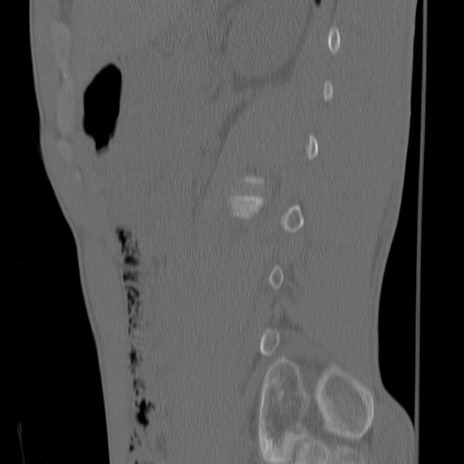

症例3 腰椎CT(矢状断像)

腰椎CT

3D再構成